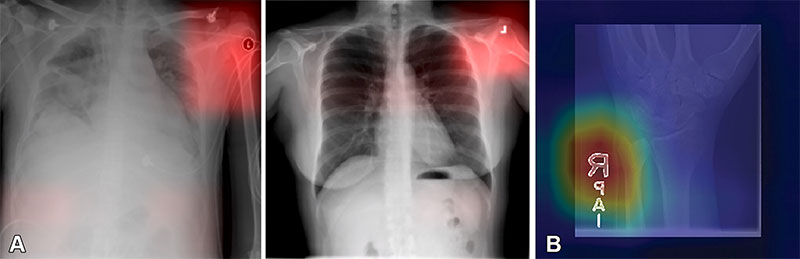

Images from a deep learning (DL) model in radiology that can learn to identify confounding features related to bias and unfair predictions, including laterality markers (image annotations indicate the side of the body being viewed [right vs left]) to identify the hospital at which a chest X-ray was obtained. Images adapted and reprinted from Zech, et al. “Variable Generalization Performance of a Deep Learning Model to Detect Pneumonia in Chest Radiographs: A Cross-sectional Study,” an open-source article, published under the Creative Commons license (CC BY 4.0). (B) Image from a DL model that can make a diagnosis of radiographic abnormality on extremity radiographs, also known as shortcut learning. Reprinted, with permission, from Yi, et al. “Deep Learning Algorithms for Interpretation of Upper Extremity Radiographs: Laterality and Technologist Initial Labels as Confounding Factors.”